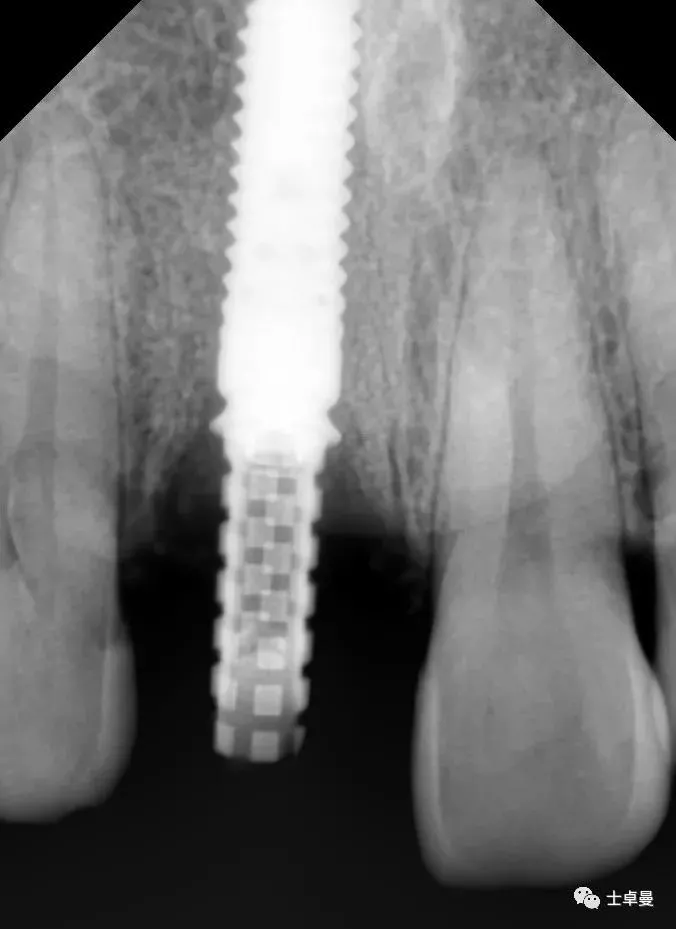

术后4个月复查,种植体周未见明显暗影

X线示,永久修复体已就位